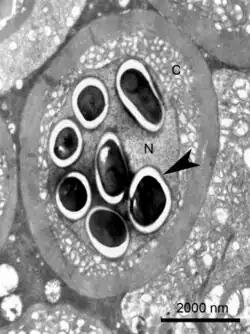

| Transmission electron micrograph of an Enterospora nucleophila-infected rodlet cell harbouring spores within its nucleus (N). No stages are visible in the cytoplasm (C) | |